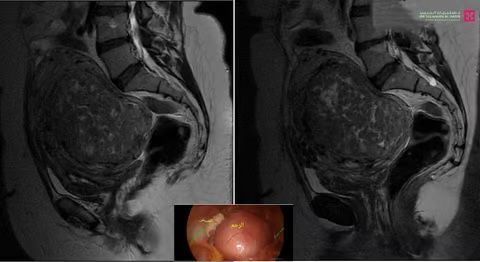

وأفادت بأن المريضة راجعت المستشفى بعد معاناة طويلة مع حزمة أعراض، أبرزها انحباس البول واحتياجها المتكرر للقسطرة البولية، وأجريت لها عدة فحوصات شملت التحاليل وأشعة الرنين المغناطيسي، التي كشفت عن وجود ورم طوله نحو “15” سم، بعدها خلص الفريق الطبي إلى ضرورة إزالة الورم عبر تقنية المنظار.

وأشارت إلى أنه بعد إتخاذ الترتيبات اللازمة أخضعت لعملية تم الدخول فيها عبر فتحات صغيرة لا تتعدى الـ”1″ سم، ودون الحاجة إلى فتح البطن، وجرى إزالة الورم بالكامل مع المحافظة على سلامة الأعضاء المجاورة والملاصقة للورم الذي يبلغ طولة “15” سم ووزنه أكثر من “1” كجم.